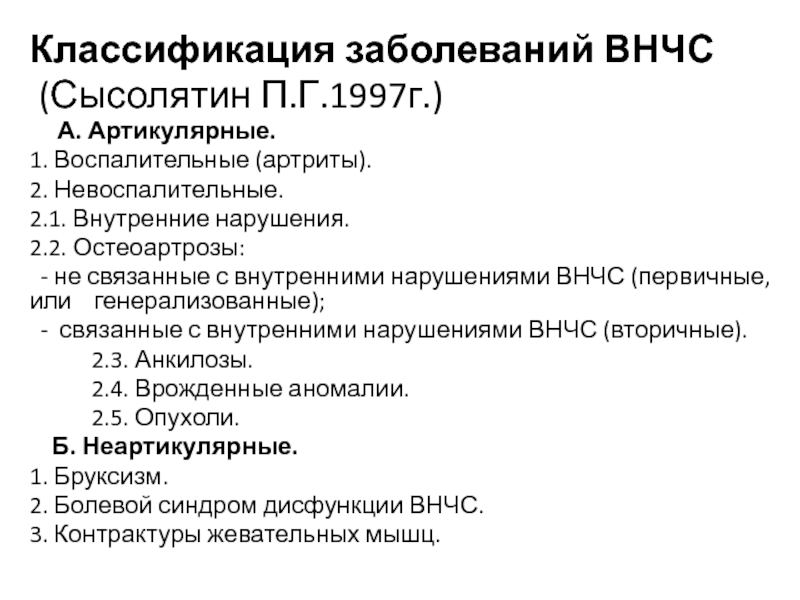

Дистрофические заболевания внчс презентация - 89 фото